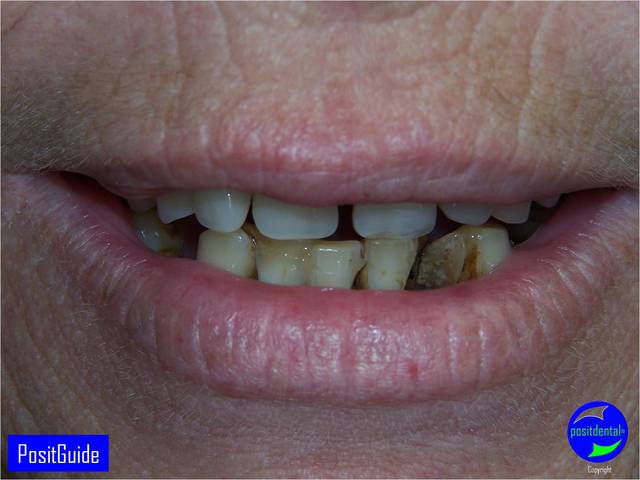

Je trouve ces cas très bien réalisés, rapide et impressionnants.

Cependant, qu'en est-il de la stabilité sur le long terme dans dans des contextes paro aussi sévère.

N'étant pasparo-compétent, qu'en est-il de la microbiologie buccale et du risque de péri-implantite à 10 ans ?